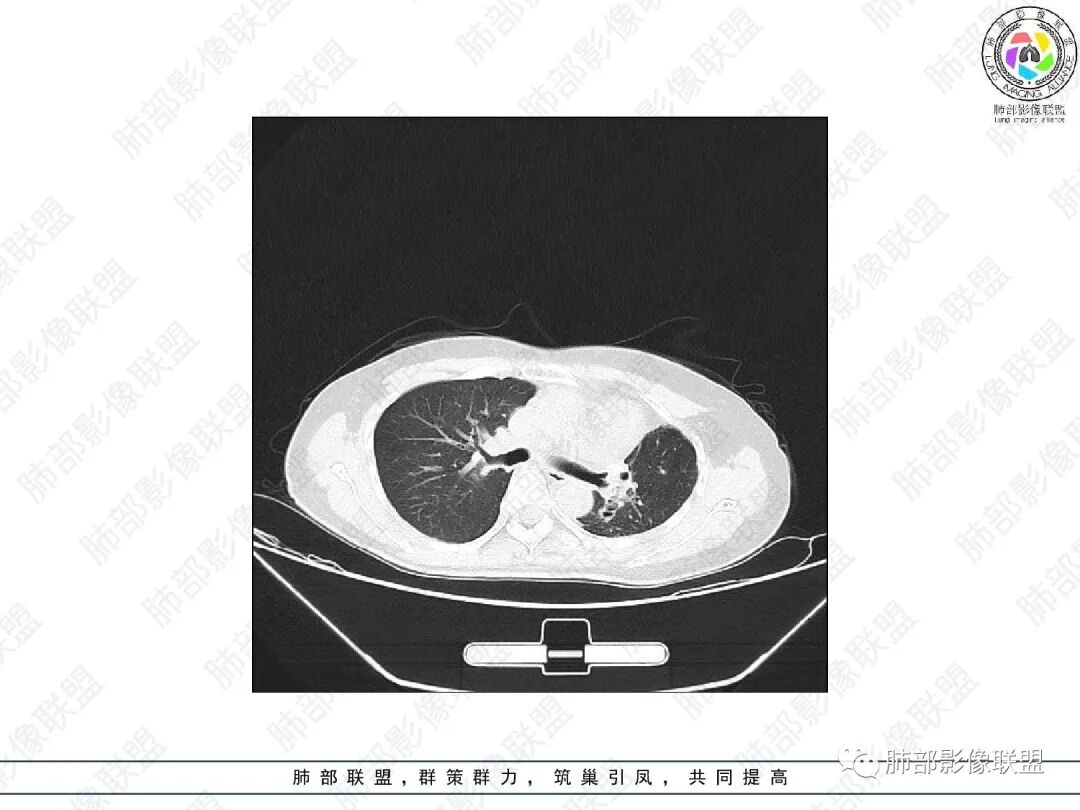

2.胸部CT:右肺上叶及中叶不规则块状影,沿支气管走行方向指套样影,支气阻塞湖嵌塞,腔内可见高密度影。灶周可见磨玻璃,外围见结节影及树芽征。左肺体积缩小,见不规则条索影、胸膜增厚,纵隔牵拉左移。

3.综合分析:结合患者病史及胸部CT主要鉴别ABPA(右肺上叶不规则块影,指套样顺延支气管方向,抗结核治疗1年,肺部病灶仍明显)及继发性肺结核TB(右肺上叶不规则肿块,其可见高密影,边缘模糊,周围卫星灶、树芽征,沿支气管爬行)。